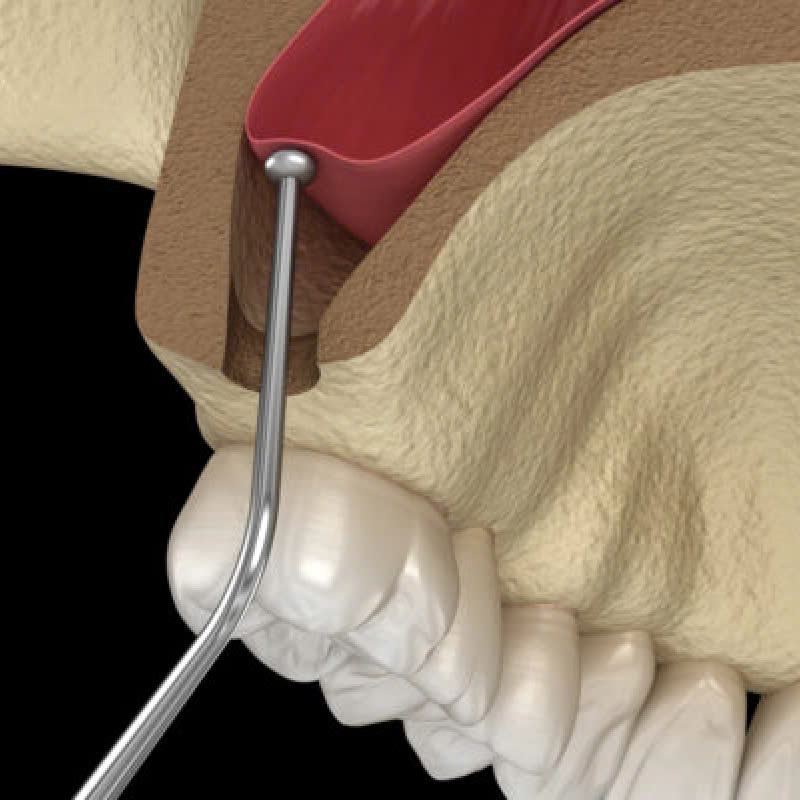

Bước 4: Nâng màng xoang

Sau khi mở đường rạch, bác sĩ sẽ cẩn thận nâng màng xoang lên cao.